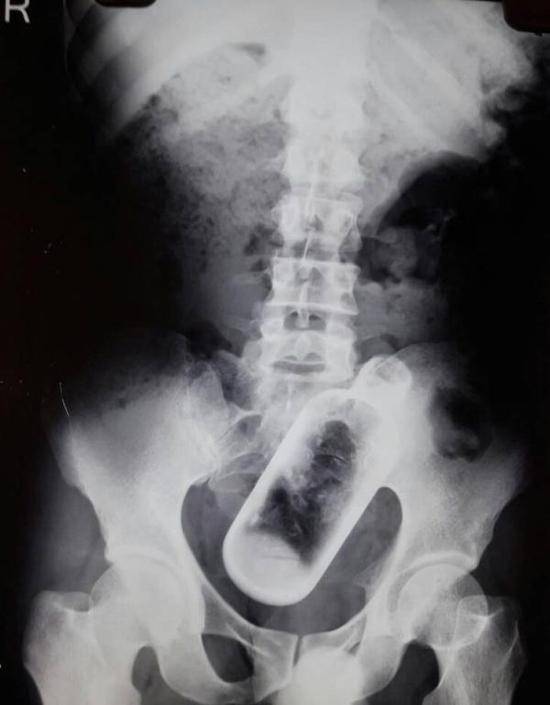

x光下看 被塞进下面的20个奇葩物体

奇葩!照x光发现酒瓶!酒瓶怎么吞进去的呢

20张x光片,原来玩儿大了啥都可以塞进屁股里.